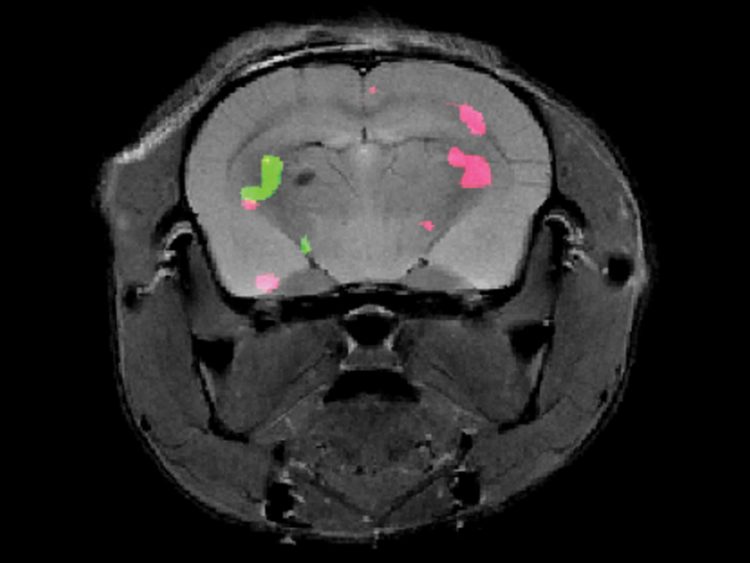

לאחר השלמת ההכנות, יישמו החוקרים את השיטה בעכברי מעבדה שהוכנסו לאחד ממכשירי ה-MRI העוצמתיים ביותר הפועלים בעולם כיום. שני הצבעים הזוהרים לא איחרו להופיע: הסריקות שהתקבלו חשפו במדויק את מיקומם של התאים אשר מבטאים את שני החלבונים המהונדסים במוחות העכברים. בכך הדגימו החוקרים את היתכנות המעקב אחר ביטוי גנים שונים במעמקי המוח והגוף באמצעות MRI. מחקרי המשך ישאפו לפתח את השיטה למיפוי מספר רב יותר של גנים בו-זמנית.